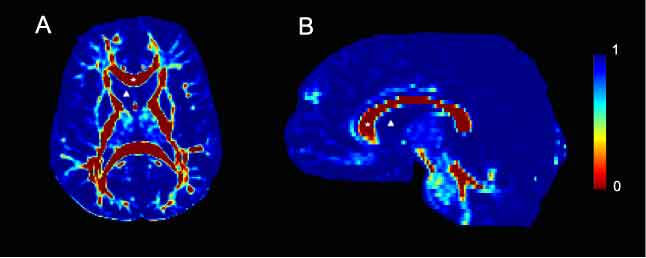

Viscosity maps derived from 2D slices of DTI data from human control subjects. Viscosity values were calculated from the corresponding diffusion tensor image and are color-coded according to the legend bar seen on the right side of the figure. A. Axial slice taken at the level of the internal capsule. The corpus callosum, marked with a star is a highly organized white matter tract and is therefore characterized by low viscosity. Conversely, the lateral ventricle, marked with a delta contains CSF and is highly viscous. B. A mid-sagittal slice. As in A, the corpus callosum is marked with a star and is characterized by low viscosity. In contrast, the lateral ventricular space, marked with a delta contains CSF and therefore has no architecture. Consequently, it is highly viscous.